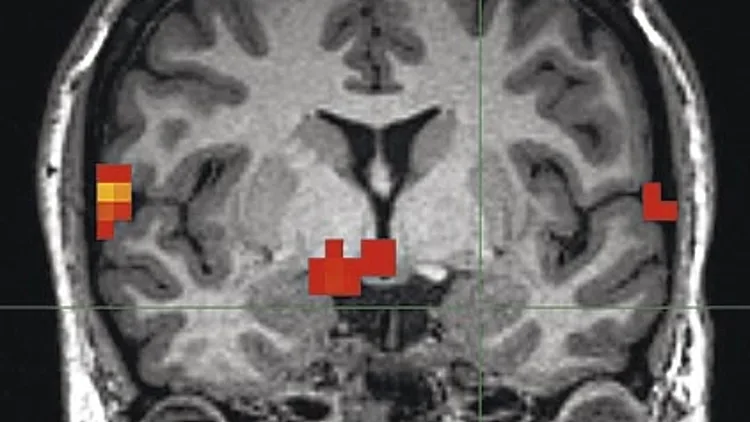

סריקת fMRI  של מוח אנושי

סריקת fMRI של מוח אנושי | צילום: Popular science